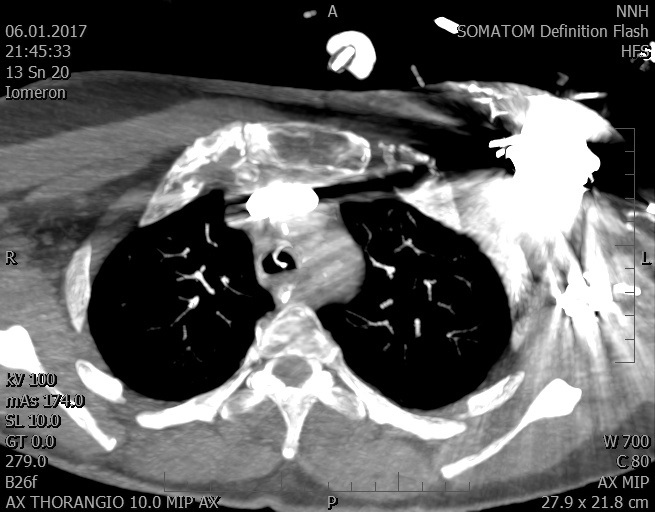

Video 2 - Echokardiograficky byla zjištěna těžká dysfunkce dilatační levé komory s nezvětšenou pravou komorou.Pro nejasnou příčinu zástavy jsme provedli i vyšetření výpočetní tomografií (CT), které vyloučilo plicní embolizaci (série 1 - soubory na konci článku). V den přijetí při přetrvávající oběhové nestabilitě byla nemocná opakovaně defibrilována pro fibrilaci komor se stabilizací rytmu po podání amiodaronu a mesocainu. Dle hemodynamických měření se jednalo o těžký kombinovaný šok. Vstupní laboratorní vyšetření bylo bez větších pozoruhodností. Posléze jsme doplnili anamnézu od příbuzných a zjistili, že pacientka užila do dvou hodin před srdeční zástavou první tabletu amoxicilinu na lehký respirační infekt. Při nevýtěžnosti vstupních vyšetření a nových anamnestických informacích jsme doplnili 14 hodin po kolapsu vyšetření koncentrace tryptázy v séru, která byla extrémně zvýšena (tabulka 2), což nás vedlo k podezření na anafylaxi.